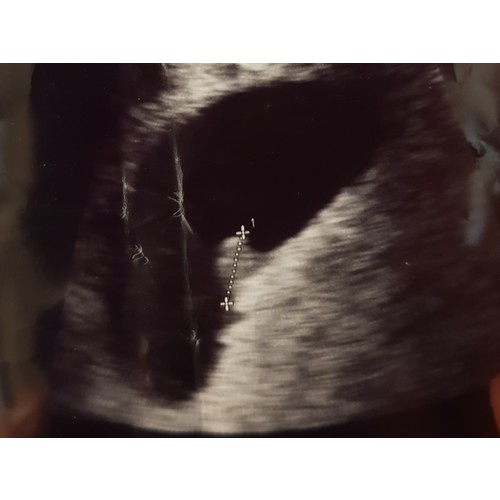

Deze echo was ik 6w3d (ik dacht zelf verder te zijn). Ook bij mij dachten ze dat t niet goed was, omdat het te klein zou zijn. Ben op dit moment inmiddels 17w zwanger. Houd hoop en ik duim met je mee!